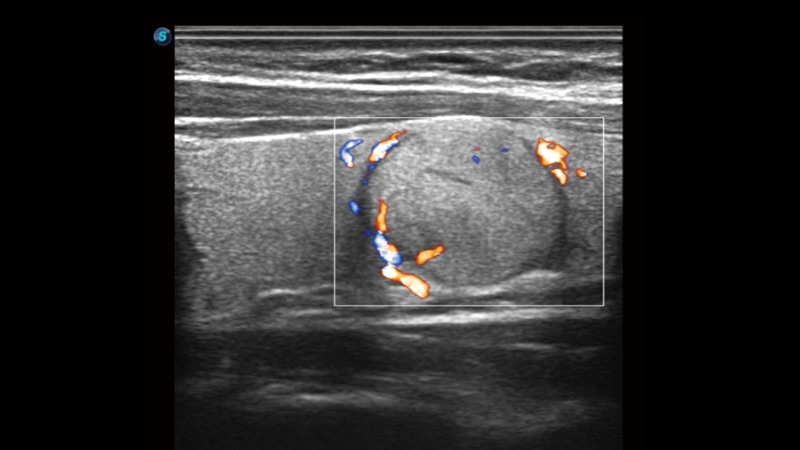

凭借开立医疗先进的成像技术和优异的探头技术提供的清晰的图像表现,您可以更自信地做出临床决策。